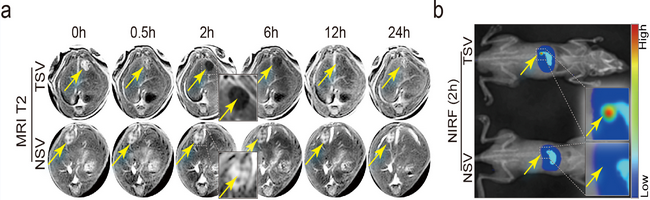

納米藥物的MRI(a)-NIRF(b)雙模態活體顯像

附屬第一醫院臨床研究中心和腫瘤中心在前期研究中,收集了大量肝癌臨床標本和患者隨訪數據,通過大規模篩選,鑒定出PBOV1等一系列肝癌相關基因,并證實PBOV1確實是肝癌患者的不良預后因素。在進一步的體外功能實驗中發現,PBOV1可通過調控β-catenin信號通路增強肝癌干細胞的功能,進而促進肝癌進展和轉移,具有作為肝癌特異性基因治療位點的可能性。但是,目前肝癌治療基因的體內載體問題仍未得到完全解決。所以,該團隊利用帥心濤教授長期研究開發的肝癌細胞靶向化納米載體平臺,將治療基團導入肝癌模型,實現對肝癌細胞的精準體內抑制。更為巧妙的是,該納米載體在進行肝癌體內基因治療的同時,可以作為高靈敏度的分子影像探針,方便地進行MRI-近紅外熒光多模態活體成像,實現治療過程和治療效果的實時顯像,動態展示納米藥物的體內實時分布和病灶在治療過程的變化,便于后期個體化治療技術的開發。